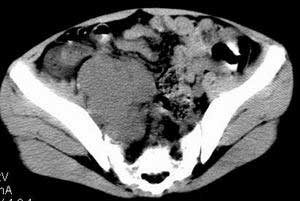

| 患者,男,9岁,因右下腹包块入院,血象不高,不规则发热,常超40度。 平扫: ![]() ![]() ![]() ![]() ![]() ![]() ![]() ![]() ![]() ![]() ![]() ![]() ![]() ![]() ![]() ![]() ![]() ![]() 增强: ![]() ![]() ![]() ![]() ![]() ![]() ![]() ![]() ![]() ![]() ![]() ![]() ![]() ![]() jiajie发言:骶椎右前区不规则软组织肿块,边缘光整,密度均匀,增强后均匀强化,右腹股沟区可见肿大淋巴结,临床有时发热,考虑淋巴瘤,儿童盆腔肿瘤应与神经母细胞瘤和横纹肌肉瘤鉴别。 longzhanghui发言:印象:盆腔右后壁不规则软组织肿块,并向前延伸.似为多个肿块融合,呈中等强化.初步考虑淋巴瘤. 听蝉观竹发言:右侧髂内、外组淋巴结肿大,从其形态和融合的情况看,同意大家意见-----考虑恶性病变,但是9岁男孩还要注意检查睾丸情况,有无隐睾? 常常类似情况是隐睾发生精原细胞瘤淋巴结转移,这个病例也要注意这一点!!! 广东凌发言:大家好,在这里我想说一下个人观点,我建议上传图片的同志能否辛苦一点就是把病史和图片都上传完整一点,比如这个病人的腹膜窗,并且这个病人的肠道的准备也是不怎么好,就从现有的质料看:病灶属于淋巴结肿大当无大的争议,有融合趋势,其内无坏死,边缘强化为主,故考虑:淋巴瘤!建议用腹膜窗看一下和肠道的关系! 阿圣发言:病灶属于淋巴结肿大当无大的争议,有融合趋势,其内无坏死,边缘强化为主,故考虑:淋巴瘤 结果是:淋巴瘤 病例来源:ct762。由宁静致远发布: http://www.radinet.com.cn/forum_view.asp?forum_id=4&view_id=2182 |